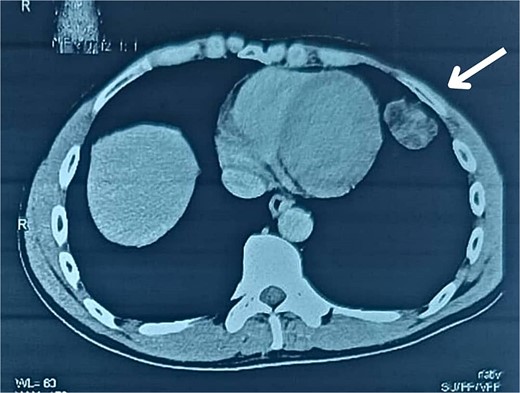

A 38-year-old male educator and part-time farmer with no notable cancer history in his family and a non-smoking background sought medical attention. His medical records included a left inguinal hernia repair two years prior and an ischemic stroke six years ago, for which he was undergoing ongoing treatment with clopidogrel, aspirin, and rosuvastatin. The patient reported swelling in the right inguinal region, without any other symptoms. The patient was prepared for surgery to repair the hernia. Upon opening the hernial sac, a thickened wall was observed. Aspiration was conducted to exclude bladder involvement, yielding cloudy, serous fluid indicative of ascites and omental thickening. Based on these observations, samples from the hernial sac wall (peritoneum), omentum, and ascitic fluid were submitted for histopathological analysis, and the hernia was repaired (Fig. 1). Peritoneal surgical biopsy showed that the peritoneal tissue fragments involved epithelioid cell malignant neoplasms with tubular and papillary formations and stromal infiltration. An IHC study revealed Calretinin and CK5/6 markers (mesothelial cell markers) were diffusely positive in the tumor, leading to a diagnosis of malignant mesothelioma. (Fig. 2 and 3) CEA levels were assessed and found to be within the normal limits. Contrast-enhanced computed tomography (CT) of the chest, abdomen, and pelvis revealed a 58 × 31 mm lobulated mass with multiple septate cavities in the lateral and basal pleura of the left lower lobe (Figs 4–6). The scan also showed thickening of the omentum, mesentery, and peritoneum, consistent with a left pleural mesothelioma with peritoneal and omental metastases. Oncologists diagnosed the patient with stage 4 pleural mesothelioma. The patient was determined to require oncological treatment consisting of eight cycles of cisplatin combined with gemcitabine. Unfortunately, the patient died during the fourth chemotherapy cycle.